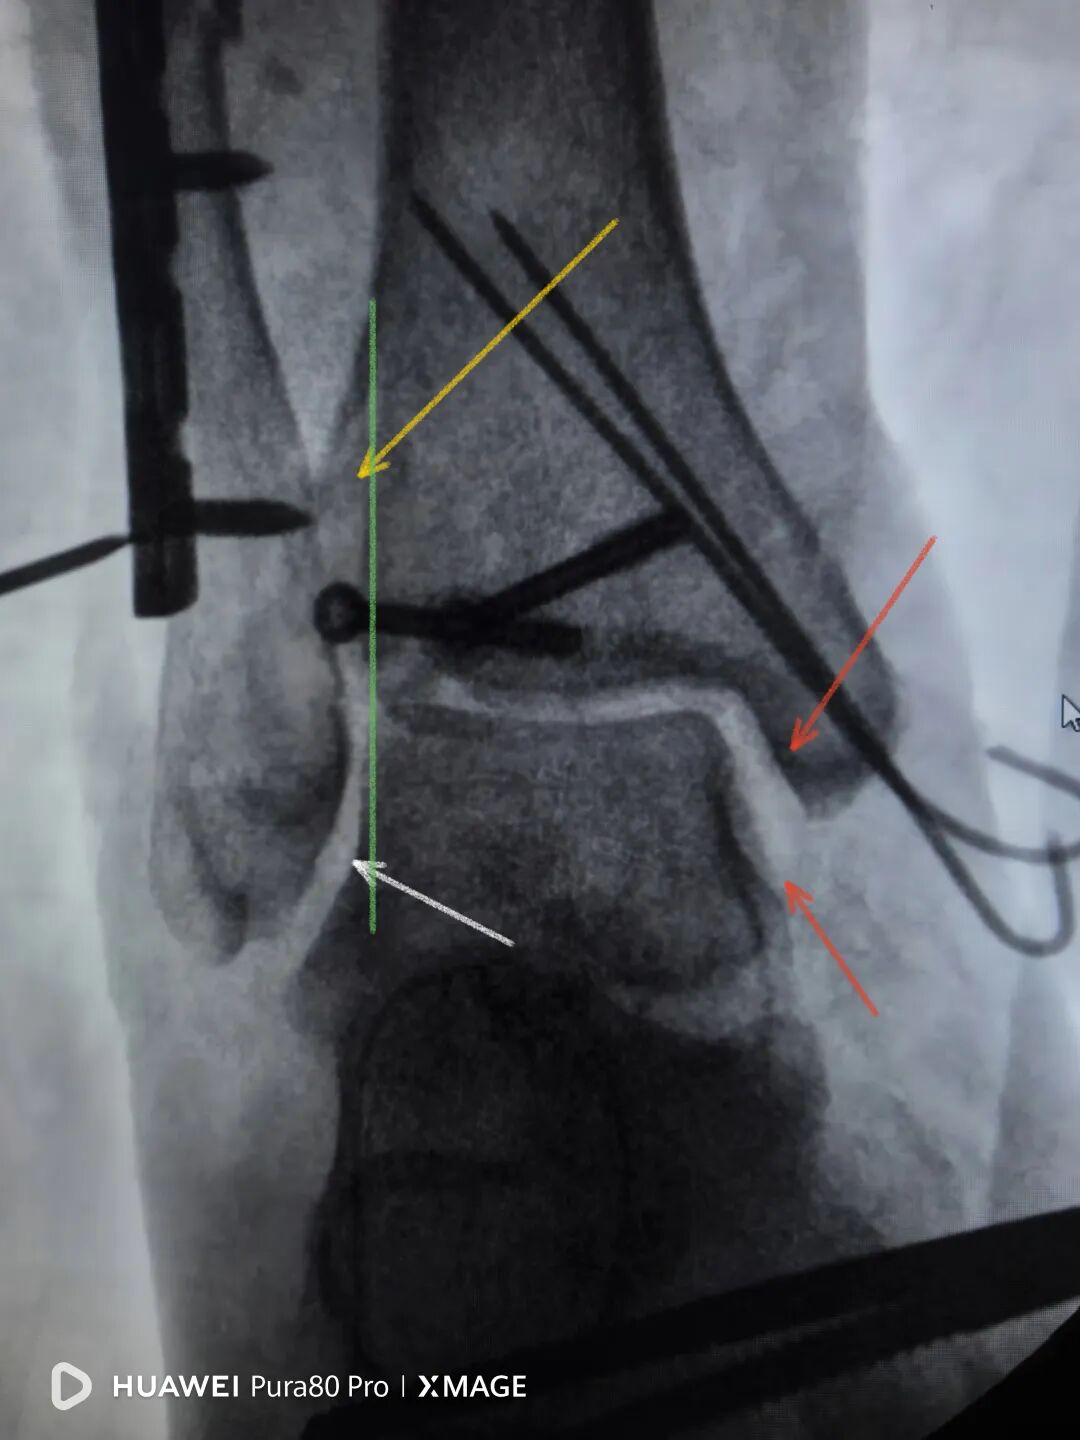

拉力钉40,拉过了,复位过头了

图片

换钉子,调整下方向

解剖复位